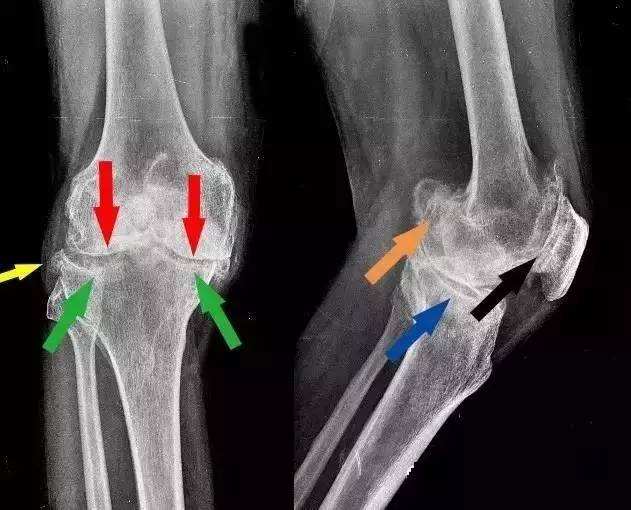

2、骨刺,只是X光片上看起来很尖,实际上并不是

是的,虽然X光片上看骨刺都是尖尖的,好像尖刀一样,但实际上,骨刺并不是尖的,而是钝的。

骨科医生在做手术时都会知道,那些在X光片上看起来尖尖的骨刺,在切开后会看到,其实骨刺表面包着一层圆润钝钝的软骨或结缔组织。只是这层圆润钝钝的软骨和结缔组织在X光片上不显示,只显示下面的骨头,所以尽管在片子上看骨刺好像是尖尖的,但是其表面其实是包着一层圆润的软骨的,并不会扎伤什么。